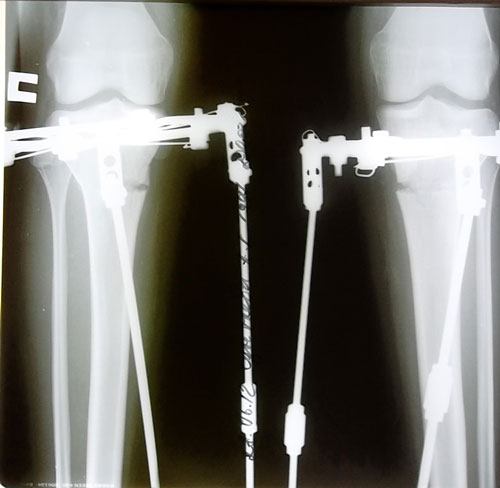

рентгеновские снимки на 11- ый день после операции. Кости выровнены, вышла на фиксацию!

Дата операции 18.06.2012г.

Аппараты сняты 22.08.2012г.

Аппаратная жизнь 64 дня.